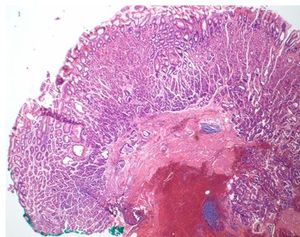

Fundic gland polyps are the most common form of gastric polyps. Giant FGPs, however, are extremely rare.